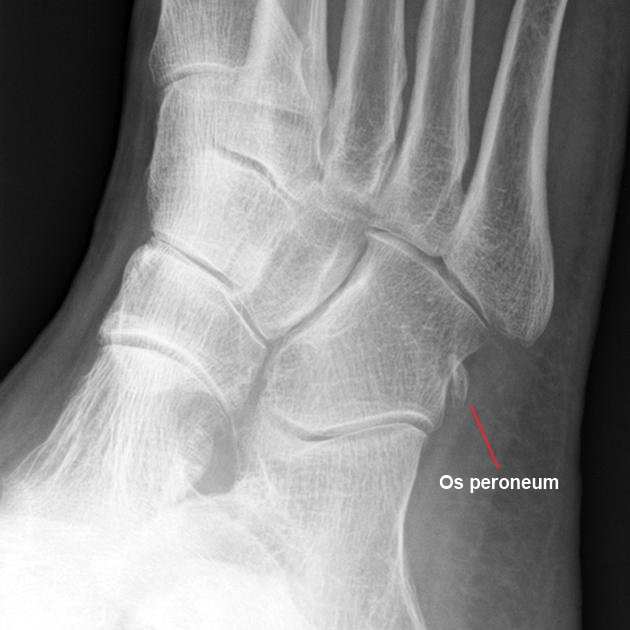

La radiografía es el estudio de primera línea para la exclusión de fracturas del maléolo lateral o el calcáneo, artrosis o cuerpos libres. También es útil para observar migración del os peroneum en ruptura del tendón del peroneo largo.

Más importante aún, las radiografías permiten identificar una fractura del borde, que es una avulsión del retináculo peroneo superior del maléolo lateral. Una proyección en estrés del astrágalo también es útil: si hay más de 15° de inclinación, puede haber inestabilidad astragalina que conlleva a inestabilidad de los peroneos.

El surco y los retináculos delimitan un túnel fibro-óseo. El peroneo corto se inserta en el 5.º metatarsiano. El largo cruza bajo el cuboides hacia el primer metatarsiano y cuneiforme medial. Puede encontrarse un os peroneum en el largo (20%) y un os vesalianum en el corto (0,1%).